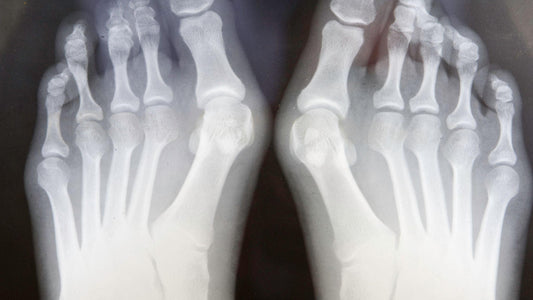

LES OIGNONS... QU'EST-CE QUE C'EST ?

Les oignons, également connus sous le nom d'hallux valgus, sont l'un des problèmes les plus courants de douleur au pied affectant les orteils et peuvent être l'un des plus douloureux....